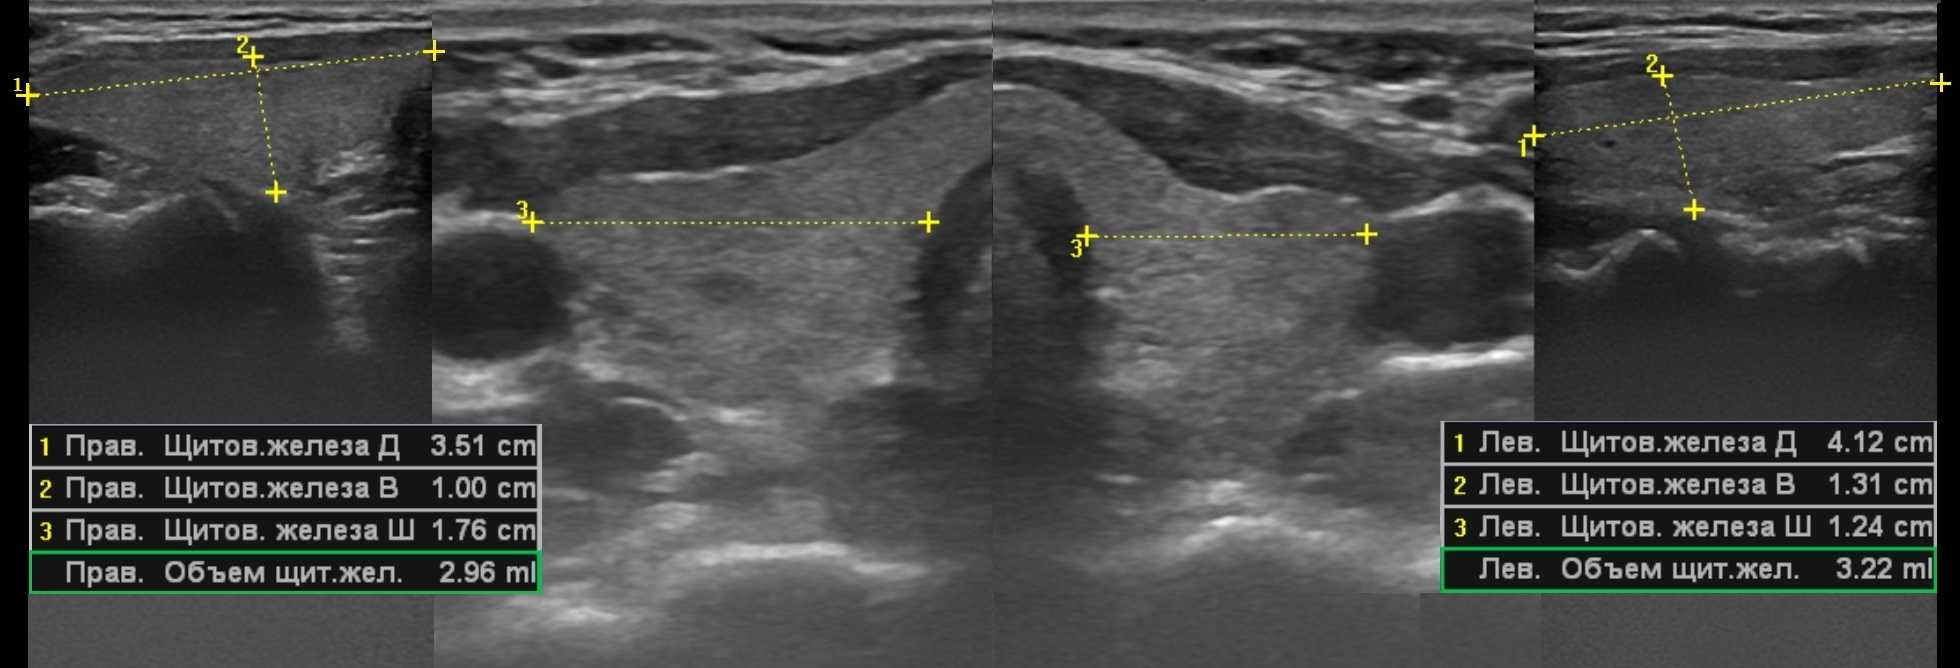

Объем щитовидной железы на УЗИ

Объем щитовидной железы равен сумме объемов правой и левой доли, перешейком пренебрегают. Требуется вывести продольное и поперечное изображение доли щитовидной железы в плоскости максимального сечения. Измеряют длину, высоту и ширину каждой доли. Объем доли щитовидной железы большинство УЗИ-аппаратов вычисляет по формуле для эллипсоида вращения: Длина*Высота*Ширина*π/6, где π/6=0,523.

Если тиреоидный объем больше нормы — это гиперплазия, а если меньше нормы — гипоплазия. Когда объем железы у верхней границы нормы, учитывают передне-задний размер перешейка: если перешеек более 3 мм до 10 лет или более 5 мм после 10 лет, то железу признают увеличенной.